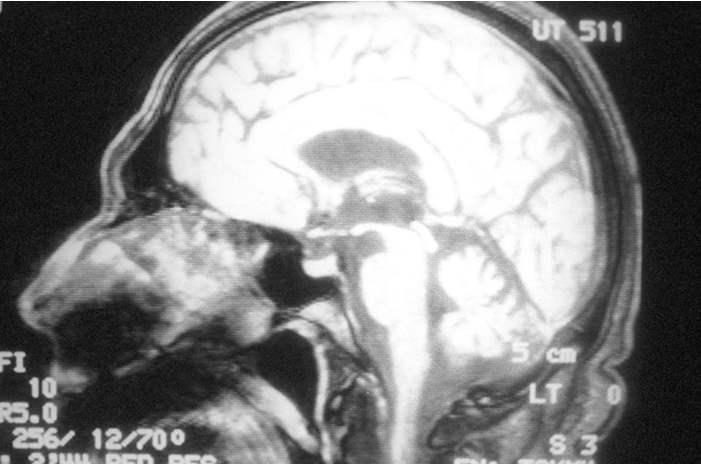

الوكيل الاخباري – جلس رجل صيني يبلغ من العمر 42 عاما، في مقهى للإنترنت لمدة 50 ساعة، لينتهي به الأمر للمستشفى، لإصابته بجلطة في المخ.

وظل الرجل في مكانه لمدة 50 ساعة دون حراك، وعندما تنبه الموظفون له، توجهوا إليه لتفقده، واكتشفوا أنه غير قادر على الكلام أو الحركة، ما دفعهم إلى نقله للمستشفى على الفور.

وشخص الأطباء إصابته بجلطة شديدة في المخ.